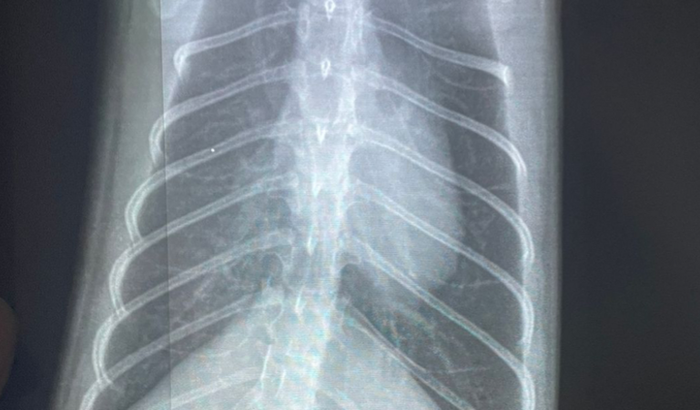

Nossa gatinha de 1 ano tem uma doença congênita chamada pectus excavatum e bronquite, nos últimos dias ela ficou bem atacada e precisa de tratamento intensivo com oxigênio, remédios, exames, etc. Para isso estamos arrecadando um dinheiro para poder fazer tudo isso e proporcionar uma vida melhor para ela